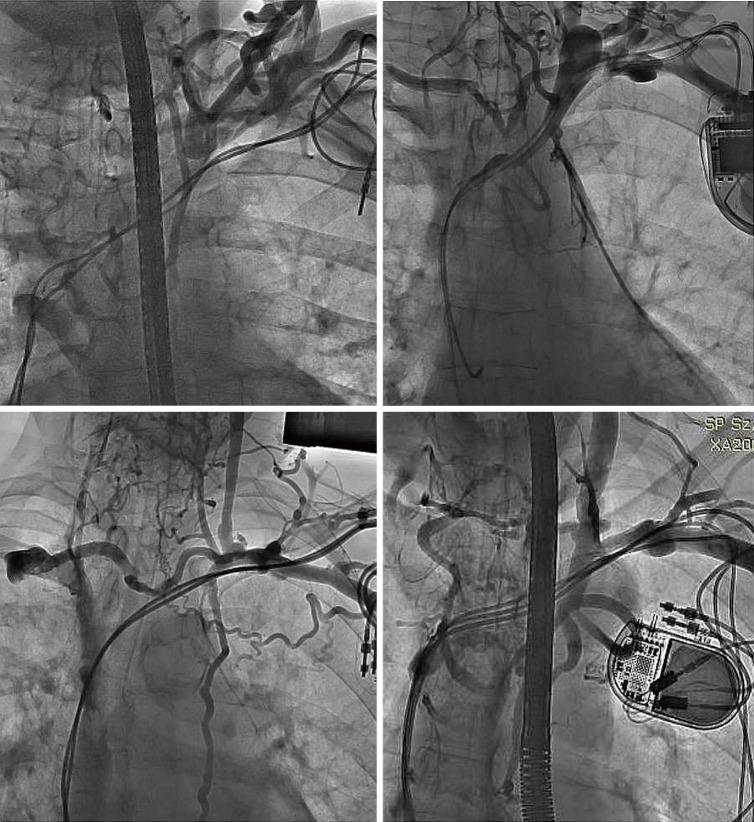

Lead-dependent venous occlusion may impede the insertion of a central venous access device (CVAD). The aim of this retrospective, cohort study was to assess the chance of implantation of CVAD in patients with cardiac implantable electronic devices (CIEDs).

We reviewed and analyzed 3,075 venograms of patients with CIEDs undergoing transvenous lead extraction (TLE) between June 2008 and July 2021. Relationship between venous patency and the chance of CVAD placement was estimated.

In 2,318 (75.38%) patients, venography showed no potential obstacles to venous port implantation on the ipsilateral side. In patients with leads on the left side, significant narrowing more often affected the subclavian vein than the brachiocephalic vein [1,595 (55.29%) 830 (28.63%), respectively] or the superior vena cava (SVC) [21 (0.73%) cases]. Furthermore, the subclavian and brachiocephalic veins on the opposite side were also narrowed [35 (2.35%) and 27 (1.24%), respectively]. The chances of port insertion were assessed as easy on CIED side or opposite side in 2,318 (75.38%) and 2,291 (97.91%) patients, respectively), as difficult insertion/questionable performance in 246 (8.00%) and 22 (0.94% patients) and doubtful or impossible insertion/questionable performance in 511 (16.62%)/27 (1.15%) patients with CIED.

(I) Varying degrees of lead-dependent venous obstruction (LDVO) is a frequent finding in patients with CIEDs; (II) the major thoracic veins on the opposite side of the chest may also be significantly narrowed; (III) venography should be considered before attempted CVAD insertion in patients with long lead dwell times or in patients after CIED removal, including planned contralateral port placement.